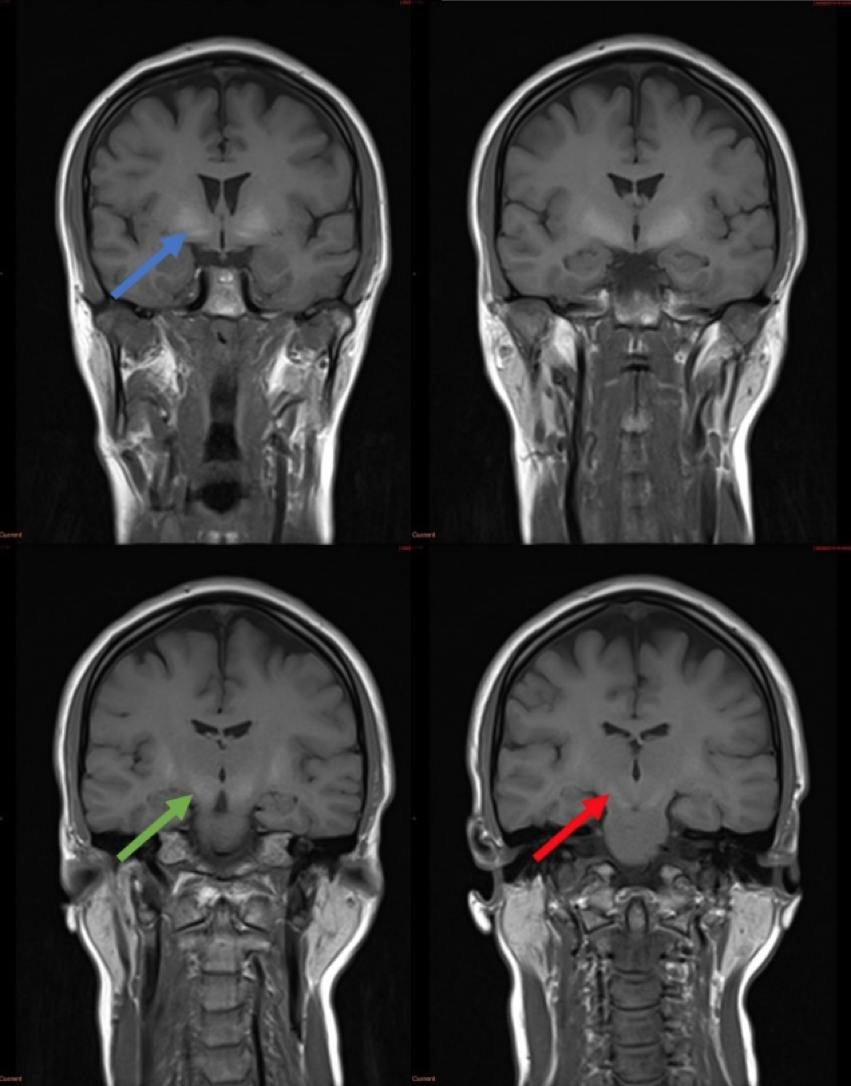

MRI of the spine demonstrated multilevel disco-vertebral degenerative changes with nerve root compression. MRI of the brain demonstrated bilateral, symmetrical T1 hyperintensity of the globus pallidus, substantia nigra, subthalamic nuclei, putamen and dentate nuclei. More subtle changes were seen in the white matter incantatory thalamic pathway and anterior pituitary gland. The appearances were highly suggestive of increased manganese deposition. Her blood manganese levels were elevated at 347nmol/L.